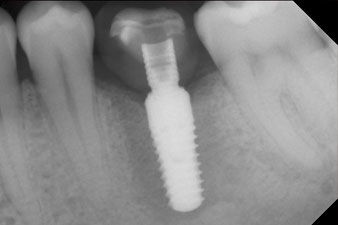

Fig. 2: Six weeks later there was an incompletely ossified alveolus in the region of the mesial root.

However, six weeks after the extraction incomplete ossification was found after preparation of the mucoperiosteal flap in the region of the former mesial alveolus.